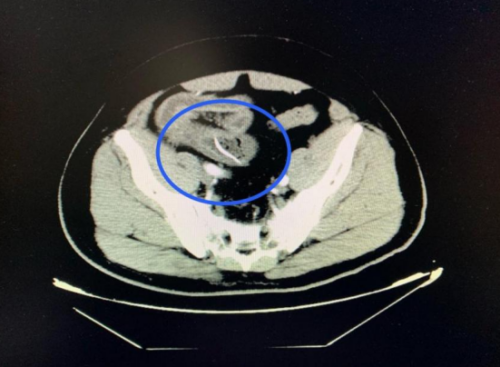

3月27日,60岁的阳宇军在进餐后出现腹部疼痛,以下腹部为主,呈阵发性胀痛,他以为没有大问题就没有去立博体育 检查。拖延两日后,阳宇军感到疼痛加剧,难以忍受,这才告知家人。家人紧急将其送入立博体育|实时赛事直播与比分|权威专家分析与体育竞猜平台 急诊医学科就诊。医生详细询问病情并进行体格检查后,立即安排了腹部 CT 扫描。CT结果显示:回肠高密度影,考虑尖锐异物并小肠穿孔、腹膜炎。结合阳宇军三天前吃甲鱼的经历,医生高度怀疑是误吞甲鱼骨导致了肠穿孔。

CT扫描可见一尖锐的鱼刺状异物